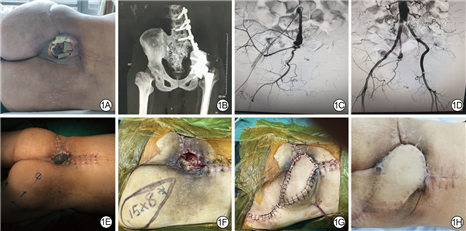

例1 男,52岁,因骨盆软骨肉瘤行放射治疗,9年后出现骶尾部放射性溃疡,经外院保守换药效果欠佳转来北京积水潭医院。既往高血压病史3年。入院体格检查见骶尾部污秽创面,基底有较多坏死组织及异物附着,创面分泌物微生物培养结果显示为金黄色葡萄球菌,入院后CT检查显示骶骨、骶髂关节受累,双侧髂血管造影显示右侧髂内动脉迂曲,有假性动脉瘤,臀上、臀下动脉管径细,左侧髂内动脉闭塞。Ⅰ期行手术清创,清除放射性坏死的骶骨及髂骨,清创后创面面积为8 cm×6 cm,行持续VSD治疗,负压值为-16.6 kPa。5 d后打开VSD材料,见创面新鲜,无明显坏死组织,同前设计并切取右侧臀上动脉穿支皮瓣覆盖创面,皮瓣大小为15 cm×8 cm,供瓣区直接缝合。术后皮瓣存活良好,创面愈合良好。术后5个月随访,皮瓣质地柔软,外观良好,供皮区愈合好。见图1。